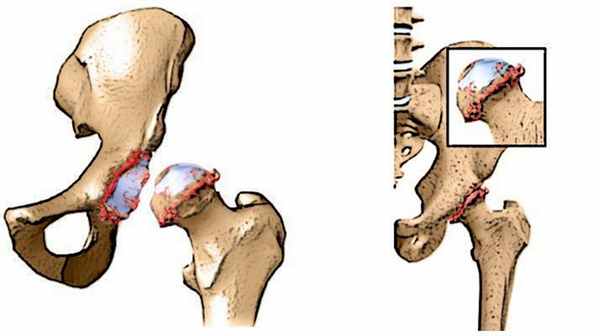

Это заболевание дегенеративного характера, заключающееся в нарушении нормальной гармонии между хрящом и костью. В результате теряется эластичность хрящевого покрова, снижается выносливость субхондральной кости к физической нагрузке. Длительные нагрузки, превышающие физиологические нормы, приводят к усиленному износу хряща, нарушению его питания и образованию в нем дефектов. Вновь образующееся опорное вещество, будучи незрелым, т. е. не обладающим ни твердостью, ни вязкостью зрелого хряща, быстро изнашивается и погибает. На месте его начинается усиленно разрастаться костная ткань, вызывая явления деформирующего артроза.

В начале болезни происходит изменения свойств суставной жидкости — в силу различных причин она становится вязкой и густой. А без должного «смазывания» суставной хрящ начинает подсыхать, а поверхность его становится шероховатой и покрывается трещинами.

В результате хрящ начинает истончаться, так как не выдерживает повышенного трения при движении. А расстояние между сочленяющимися костями сустава постепенно уменьшается. Кости как бы обнажаются из под хряща, давление на них увеличивается и они начинают деформироваться.

Артроз бедренного сустава – это прогрессирующее изнашивание и разрушение хрящевой ткани тазобедренного сустава. В результате человек испытывает сильную боль и ограничение подвижности в суставе. Это заболевание также известно как коксартроз или остеоартроз тазобедренного сустава.